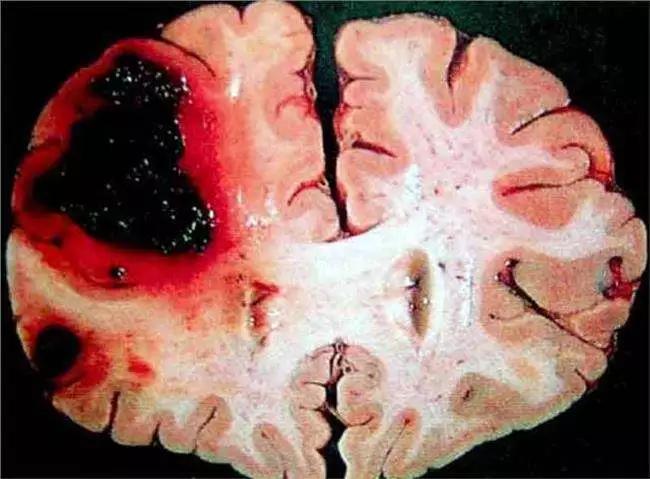

腦出血是指非外傷性腦實(shí)質(zhì)內(nèi)血管破裂引起的出血,實(shí)際上就是血管內(nèi)的血液外溢進(jìn)入顱腔侵襲腦部引起的出血。一般都會給患者造成極大的影響,那么腦出血有哪些癥狀呢?

臨床癥狀、體征常常因?yàn)槌鲅牟课灰约俺鲅坎煌憩F(xiàn)的不同,機(jī)體和丘腦以及內(nèi)腦的出血引起輕偏癱是較常見的早期癥狀,少數(shù)病例會出現(xiàn)癲癇性發(fā)作,常常是局灶型的,重癥者會迅速轉(zhuǎn)入意識模糊或者昏迷。

三、意識障礙,主要是表現(xiàn)為嗜睡或者昏迷,程度與腦出血的部位、出血量有關(guān)。